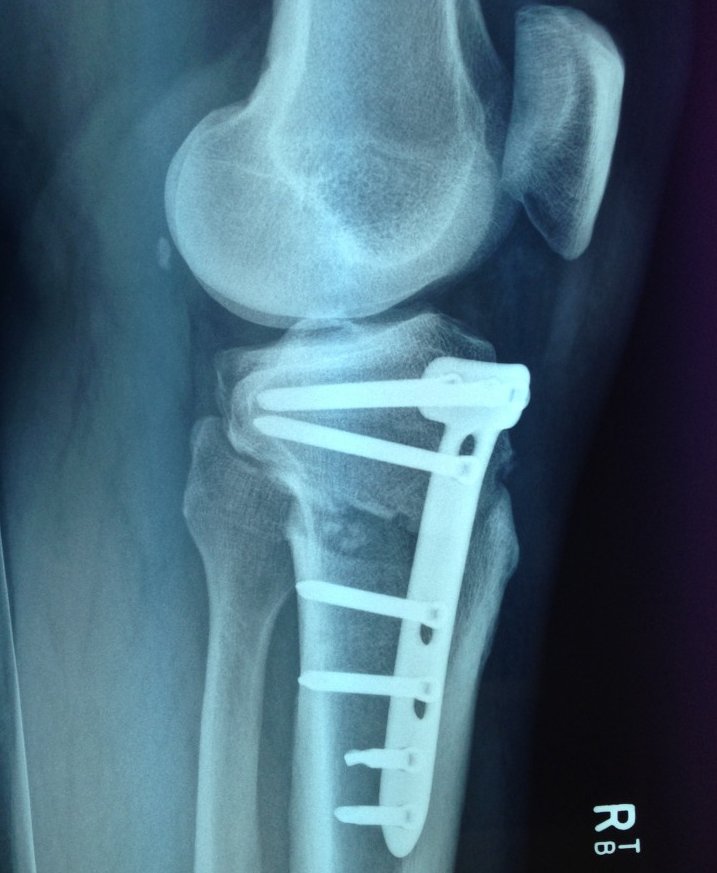

It's been over 3 years now since my last surgery and that was to have the Thomas Plate put in for a High Tibial Osteotomy (basically it was to stop bone on bone grinding in the knee...YEEK). Don't worry I wont go into the gruesome side of what was done, but I have attached the X-Ray image of the plate & screws. As you can see in the x-ray I had a T-Plate & 8 screws "installed" on the right leg.... It fixed the issue of bone on bone.